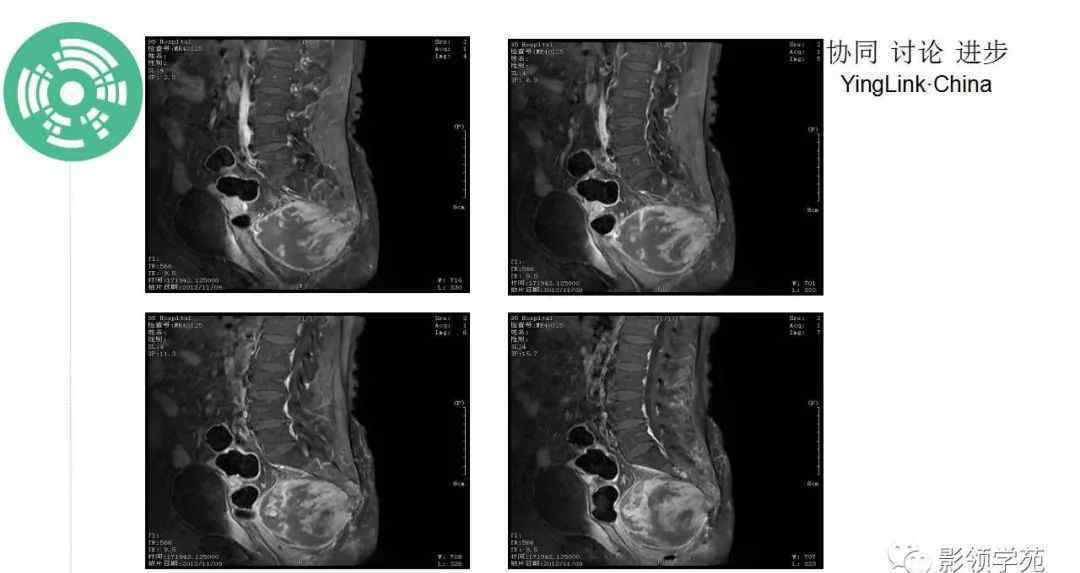

脊索瘤的影像学表现

MR: T1W1序列呈低信号或等信号,小病灶高信号代表肿瘤出血或粘液蛋白。T2W1序列显示中等或明显的高信号强度,内部低信号强度代表钙化、纤维隔膜或血液降解产物。增强后呈中、重度增强,偶有轻度或无增强,动态增强呈缓慢、持续增强。